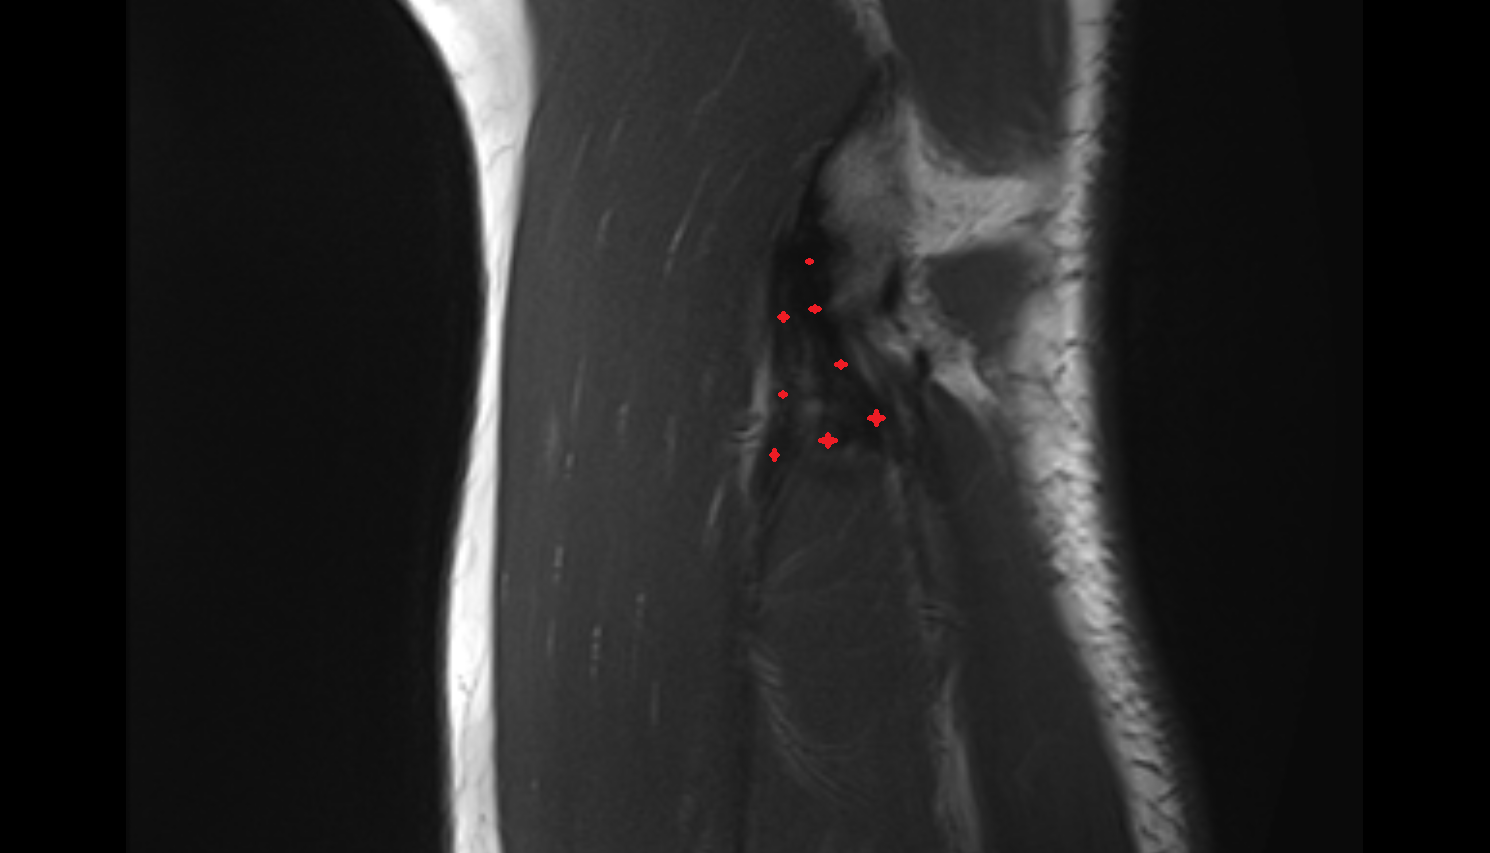

- Anterior cruciate ligament

- Posterior cruciate ligament

- Anterolateral ligament of knee